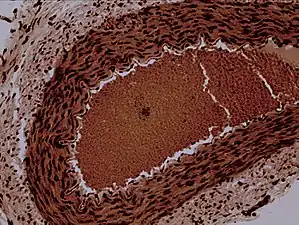

![]() Rabbit arteriole at 100X | |

An arteriole is a small-diameter blood vessel in the microcirculation that extends and branches out from an artery and leads to capillaries.[1]

Arterioles have muscular walls (usually only one to two layers of smooth muscle cells) and are the primary site of vascular resistance. The greatest change in blood pressure and velocity of blood flow occurs at the transition of arterioles to capillaries. This function is extremely important because it prevents the thin, one-layer capillaries from exploding upon pressure. The arterioles achieve this decrease in pressure, as they are the site with the highest resistance (a large contributor to total peripheral resistance) which translates to a large decrease in the pressure.[2]